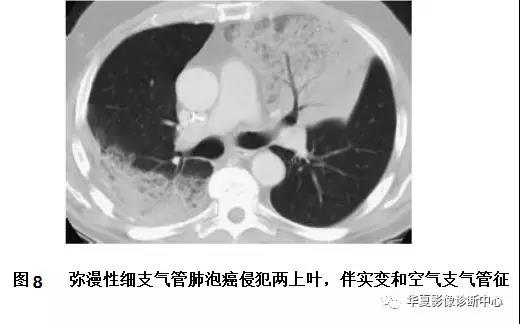

在40%的病例中,BAC呈弥漫性或多灶性肺湿润,表现为肺实变或多发的模糊结节(图7,图8,图9)。这种表现尤其见于BAC的黏液亚型。尚不清楚这种表现是由肿瘤的多中心起源还是肿瘤支气管内的播散所导致。这类肿瘤也可见匍匐生长,肿瘤细胞沿肺泡壁排列,产生黏液充填肺泡腔,导致了影像上的实变表现。常见CT血管造影征,即在实变的肺里可见CT增强后呈高密度血管影。弥漫性BAC患者会产生大量的水样痰,称为支气管黏液溢,是大量黏液产生的结果。弥漫性BAC预后不良。

图7弥漫性细支气管肺泡癌

A.胸片显示右肺基底部的实变(箭头);B.5mm层厚的CT显示多个区域的实变,含有空气支气管征,多发的边界不清的结节,这些结节呈小叶中央分布,代表气腔或腺泡结节,在弥漫性细支气管肺泡癌中很常见。